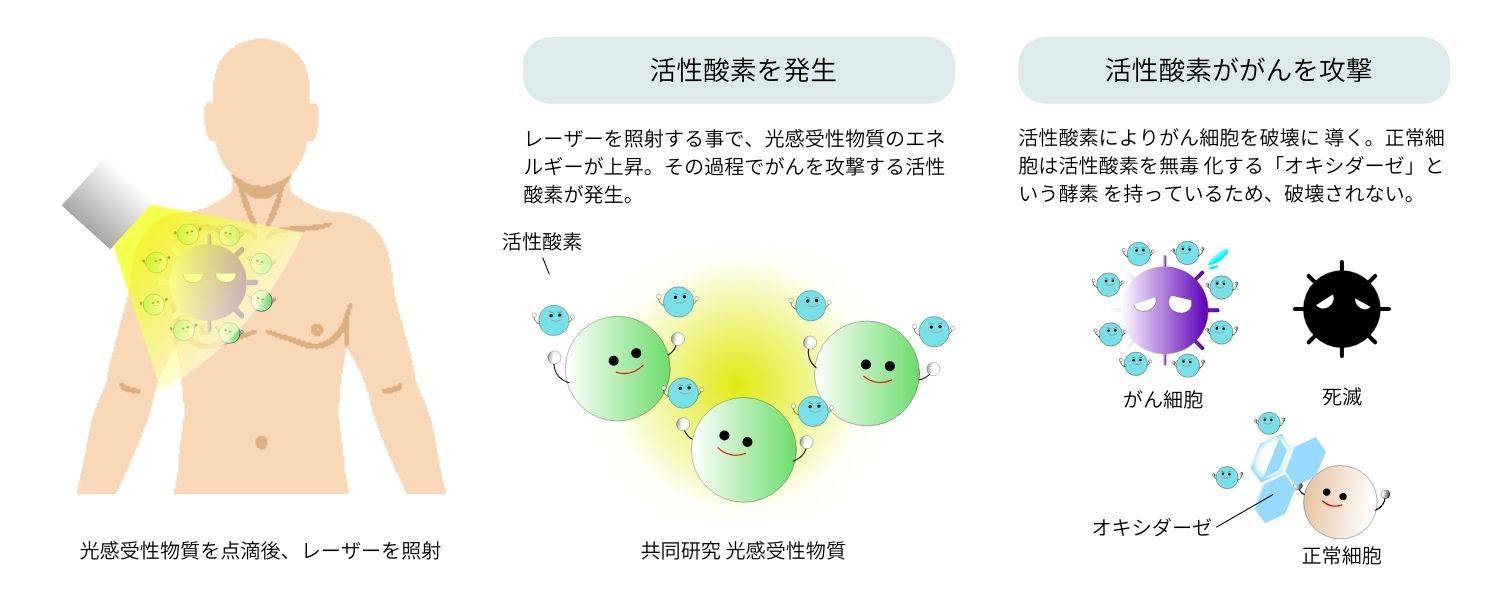

がんの光免疫療法は、光感受性物質という微細な薬剤を点滴で投与した後に、レーザー光をがん細胞へ照射する事によって、光化学反応によりがん細胞をターゲットとして破壊する選択的な治療方法です。

図のように薬剤はレーザー光によって活性化し、活性酸素を生成してがん細胞を破壊します。

光を光感受性物質に当てると、その物質はエネルギーを放出し、この過程で活性酸素が生成されます。

これを「光化学反応」と呼びます。がん細胞は活性酸素に弱く、この活性酸素によって破壊されます。

一方、正常な細胞は活性酸素を無毒化する「オキシダーゼ」という酵素を持っているため、破壊されません。

これも、副作用が少ない理由の一つです。